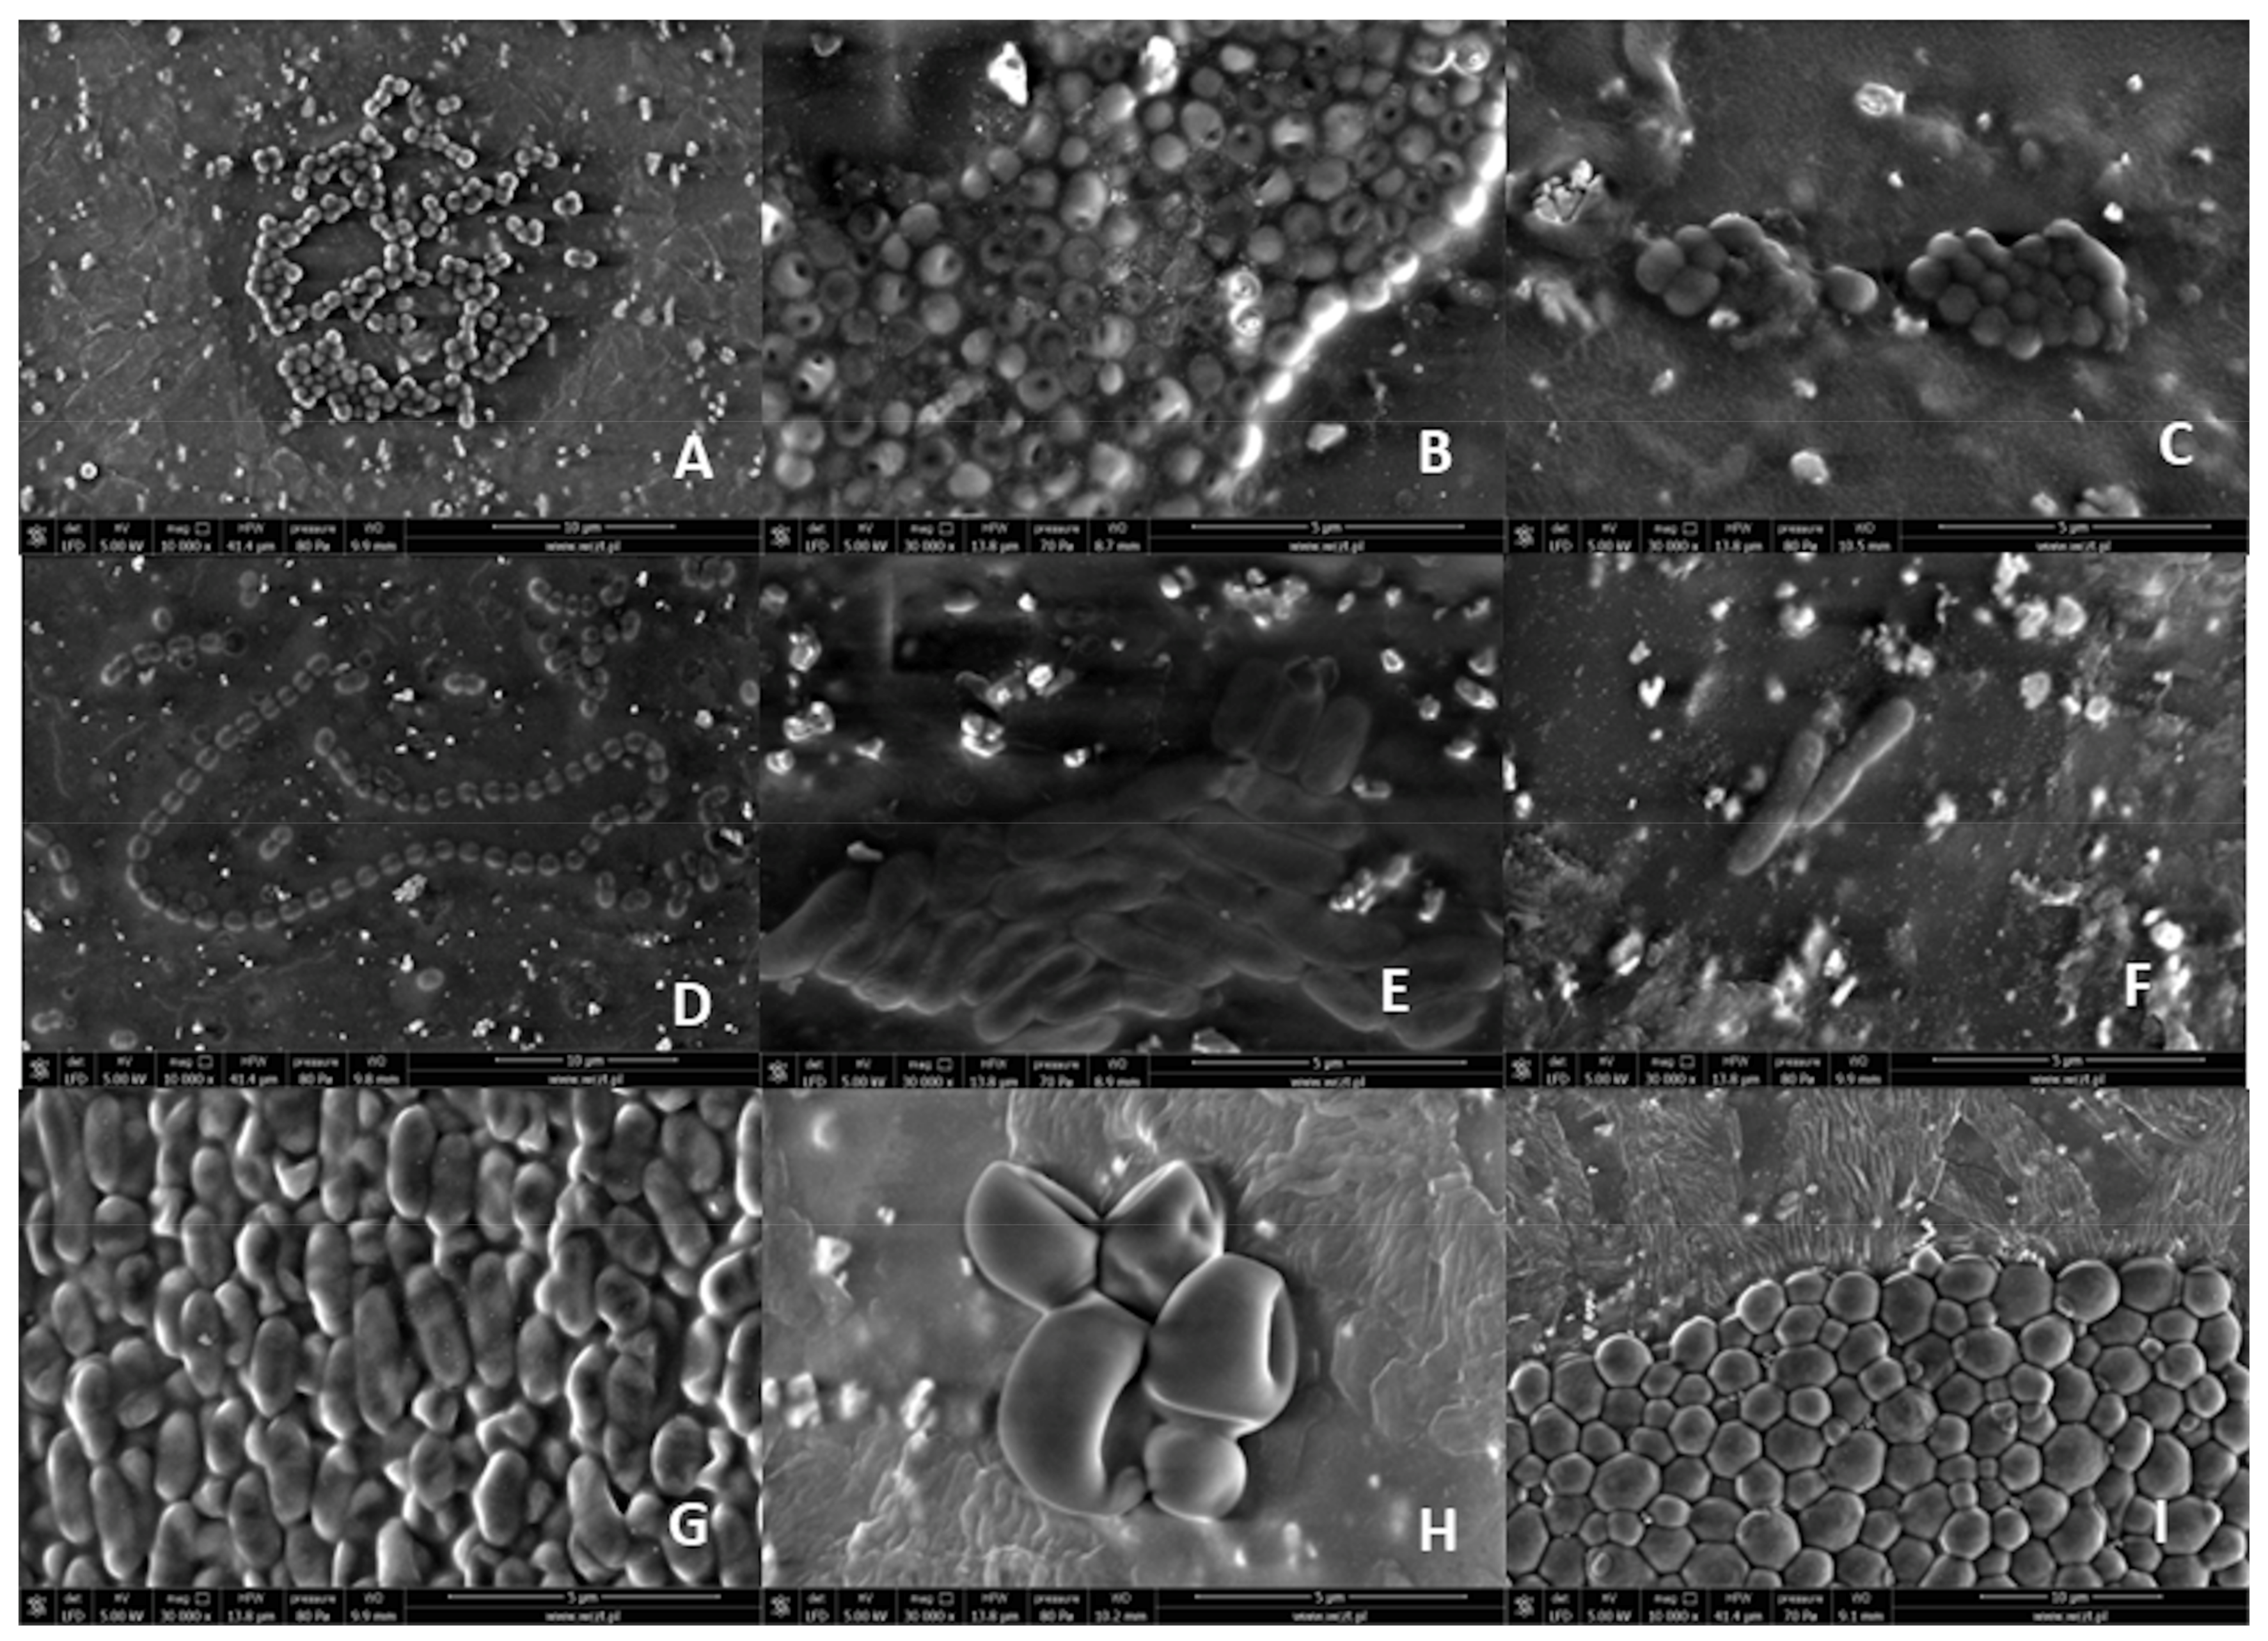

SEM images obtained during the analysis were included in this study. The images obtained after 24 and 48 h of culturing did not differ from each other. This proved the rapid colonization of central catheters in the presence of pathogens in the environment where the central catheter was located. No biofilm was observed on any of the examined catheter fragments. The SEM test was conducted shortly after the material delivery, i.e., in about 15 min. Images of the reference strains from the scanning force microscope are shown as Figure 1. Figure 1 includes representatives of individual pathogens responsible for catheter sepsis characteristic of catheter-related-sepsis in our centre. Images show characteristic bacterial cells: cocci, rod-shaped, and the image corresponds to at least one of the following features: cell division or a characteristic spatial arrangement, cell clusters compatible with a given microcolony (staphylococci, bunches streptococci). Yeast-like fungi were much larger than bacteria.

Figure 1. Scanning electron microscopy (SEM) images of reference pathogens: Gram-positive cocci: (A) Staphylococcus aureus, (B) Staphylococcus epidermidis; Gram-positive cocci—streptococci: (C) Streptococcus parasanguinis; Gram-positive enterococci: (D) Enterococcus fecalis; Gram-negative bacilli (E) Klebsiella pneumonie, (F) Escherichia coli, (G) Pseudomonas aeruginosa; yeast-like fungi of the Candida genus: (H) Candida dubliniensis, (I) Candida albicans.